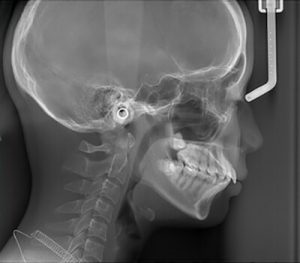

【セファロレントゲンとは?】

簡単に言うと、横顔全体のレントゲン写真です。このセファロレントゲン写真を使って、顎の大きさや位置、歯の角度などを分析します。